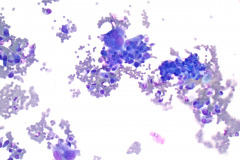

Specimen Type: FNA of Lung, Right Upper Lobe Nodule, Traditional smears with Diff-Quik and pap stain, ThinPrep® Non-Gyn

Cytologic Diagnosis: Positive for malignant cells, consistent with epithelioid sarcoma.

Biopsy / Pathologic Diagnosis: Immunohistochemistry stains are positive for AE1/AE3, EMA, ERG, and negative for CD34. Loss of INI1 nuclear expression. These results are consistent with epithelioid sarcoma. Surgical biopsy performed 8 months later diagnosed multifocal metastatic epithelioid sarcoma of the right lung upper, middle, and lower lobes.

Cytology: In fine needle aspirations of ES tumors, the specimens are usually moderately to highly cellular and the cytologic atypia can vary.6 ES tumors display a primarily single cell pattern with small, loosely cohesive clusters of cells mixed with a central fibrillary matrix.5 The cells can appear as polygonal, round, or spindle shaped with well-defined borders.5 It is common for the cells to be binucleated or multinucleated.5 The nuclei can be mild to moderately pleomorphic, and are large, round, and eccentrically placed.5 Clumped or vesicular chromatin and one or multiple small nucleoli can be observed.5 The cytoplasm of these cells can range from moderate to abundant and will be dense with small vacuoles.5 Necroinflammatory debris will often be present in the background of smears.5 In Romanowsky stains, a fibrillar metachromatic staining matrix can rarely be observed.6

Some cytologic differences exist between the two subtypes of ES tumors. The classical subtype usually presents with monomorphic, bland appearing epithelial cells with mild nuclear atypia.2 In contrast, the proximal subtype is more likely to display larger, more atypical cells along with necrosis and mitoses.5 The proximal subtype may present with a rhabdoid appearance, in which sheets of large, rounded cells display eccentric, vesicular nuclei with prominent nucleoli and eosinophilic cytoplasmic inclusion bodies.1 Overall, the cytologic differences between the subtypes are minimal and they can both present in similar cytomorphologic patterns.6